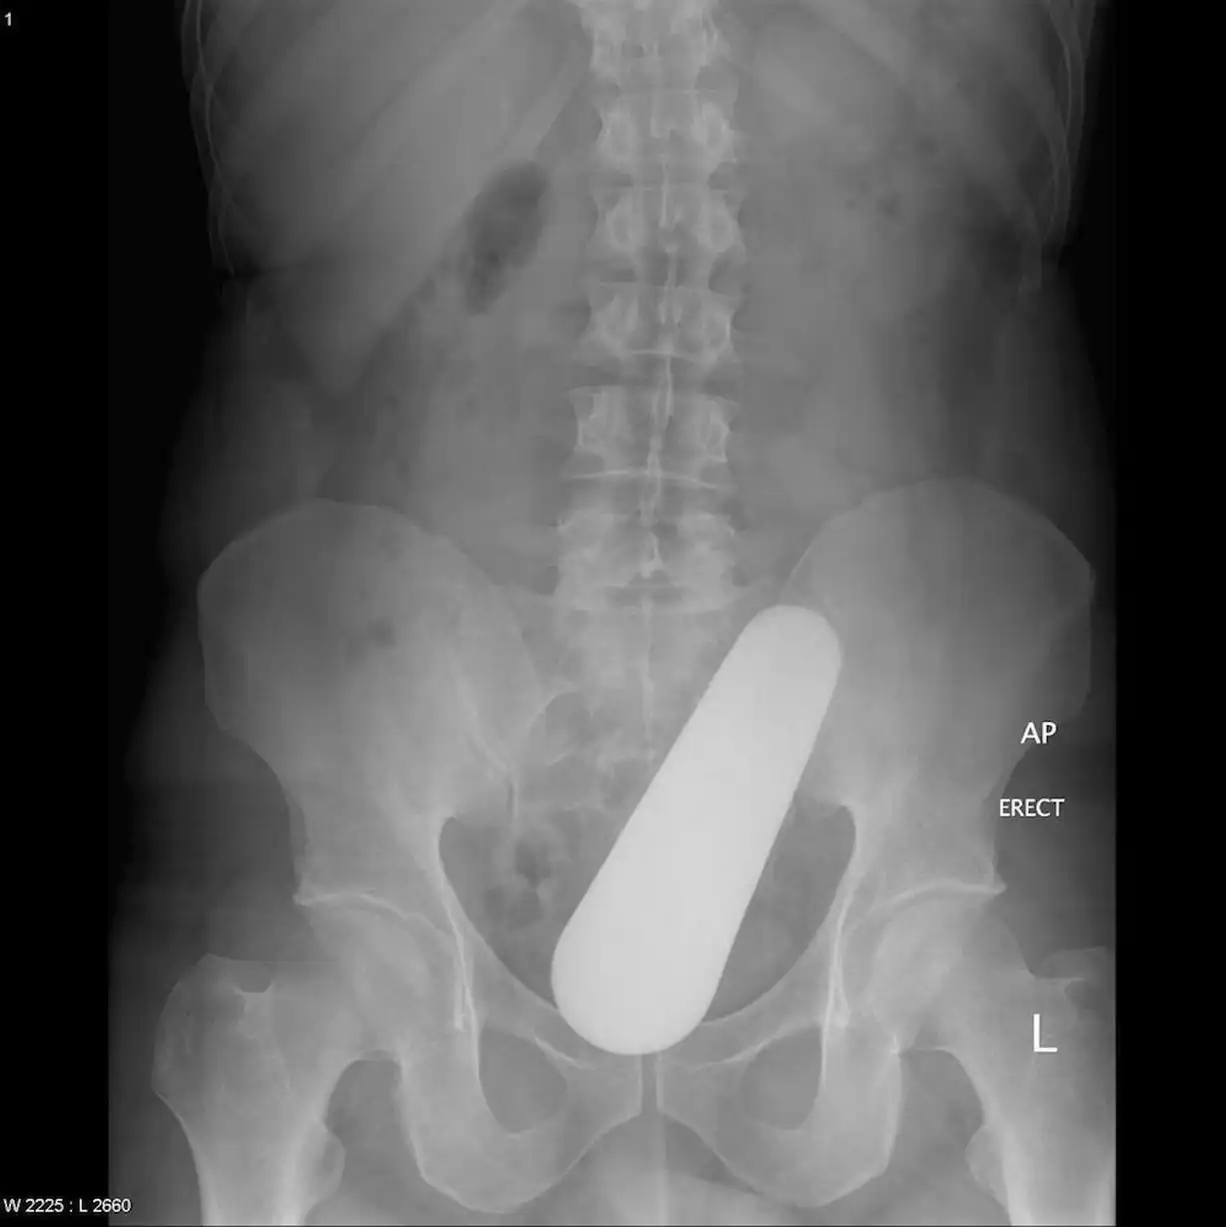

Врачебные находки в интимных местах

Или как впихнуть невпихуемое :lol: